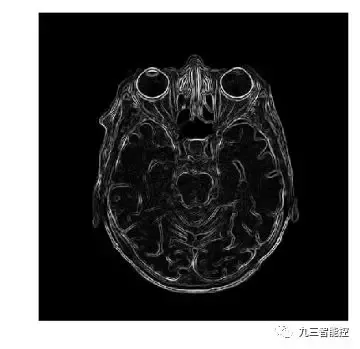

(4)神经系统图像

边缘检测(梯度模)

图像的梯度模的定义如下,它可以同时检测图像的水平和垂直方向的变化。